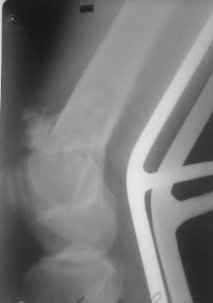

Уважаемые коллеги, прооперирована пациентка антеградным штифтом Остеомед, костная пластика не проводилась. Выбранный штифт по каналу бедренной кости на фоне отсутствия переднего кортикала в канале не центрируется. Технически неприятно, отсутствие передней и внутреннебоковой стенки до зоны мыщелков сильно затрудняло репозицию. Получилась вот такая картина. После стабилизации - очевидное повреждение ПКС и боковая нестабильность. В общем и далее будет чем заняться. Нам и в дальнейшем будет очень интересно мнение коллег.

Молодцы, здорово получилось. Как ввдили самый дистальный винт? Надколенник не мешал?

А надколенник мешал слегка, но... штифт слегка предмоделирован до начала операции и угол введения дистального винта был градусов на 15 изменен, в итоге серьезной помехи надколенник не создал.

Общее время нахождения в операционной составило около 3,5 часов, бедро заняло около 2-х. У больной имелся также перелом в/3 костей контрлатеральной голени, там тоже пришлось помучиться, репозиция была не без проблем), остеосинтез проксимальным эскпертом остеомед. Работа ЭОПа составила около 5 минут.

Повторюсь - "Выбранный штифт по каналу бедренной кости на фоне отсутствия переднего кортикала в канале не центрируется", при устранении угловой деформации штифт фактически не попадал в дистальный отломок, отсюда и мучения...